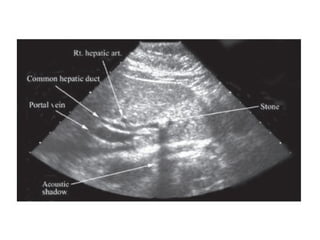

 Ultrasound abdomen.

Choledocholithiasis

Primary bile duct stones

 Stones that form in bile duct itself.

 The bacterial enzyme hydrolyzes

bilirubin diglucuronide into free

bilirubin which then precipitates and

form a complex with cholesterol.

 Principal composition of the pigment

stone is calcium bilirubinate.

 Pigment stones are either brown or

black.

 Brown stones are associated with

infection in the biliary tree.

 Black stones are associated with

chronic hemolytic diseases.